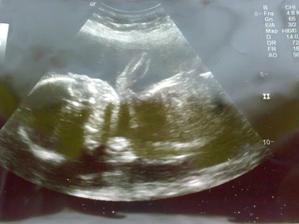

A v dubnu 2010 jsem si náhodně udělala testík a nevěřícně jsme všichni koukali, že bude mít brášku nebo ségru :o)